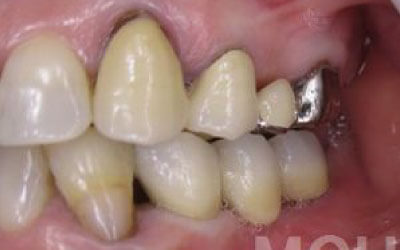

歯が抜けた後の治療について、多くの方が悩まれています。

特に、抜けたのが前歯ですとなおさら気になりますよね。

今回のご質問ですが、抜けた部分の骨が薄いなどの理由で「インプラントはできない」と言われた可能性があります。

前歯はもともと骨が薄く、歯が抜けると時間の経過とともにさらに骨が痩せてきてしまうので、インプラント治療の難易度が高い場所です。

ただ結論からお話すると、インプラント治療は可能です。

なぜなら、もし仮に骨が薄くても、骨の治療によって厚みが増せば、安全にインプラント治療が行えるからです。

なお、前歯のインプラント治療をご希望の方には、注意していただきたい点が4つほどあります。

1)インプラント治療を行う前に、骨の治療が必要かもしれません。

2)骨の治療から始めると、その分、治療期間が長くなります。

3)骨の治療は、通常のインプラント治療よりも難易度が高いため、経験の豊富な先生やインプラント認定医のいる歯科医院で治療を受けることをお勧めします。

4)骨の状況をしっかり把握するためにも、CT撮影が必須となります。